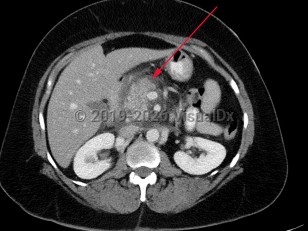

Acute pancreatitis is an acute inflammatory process of the pancreas characterized by the sudden onset of severe abdominal pain, most commonly epigastric in location, often with associated radiation of pain to the back. Nausea and vomiting are common associated symptoms.